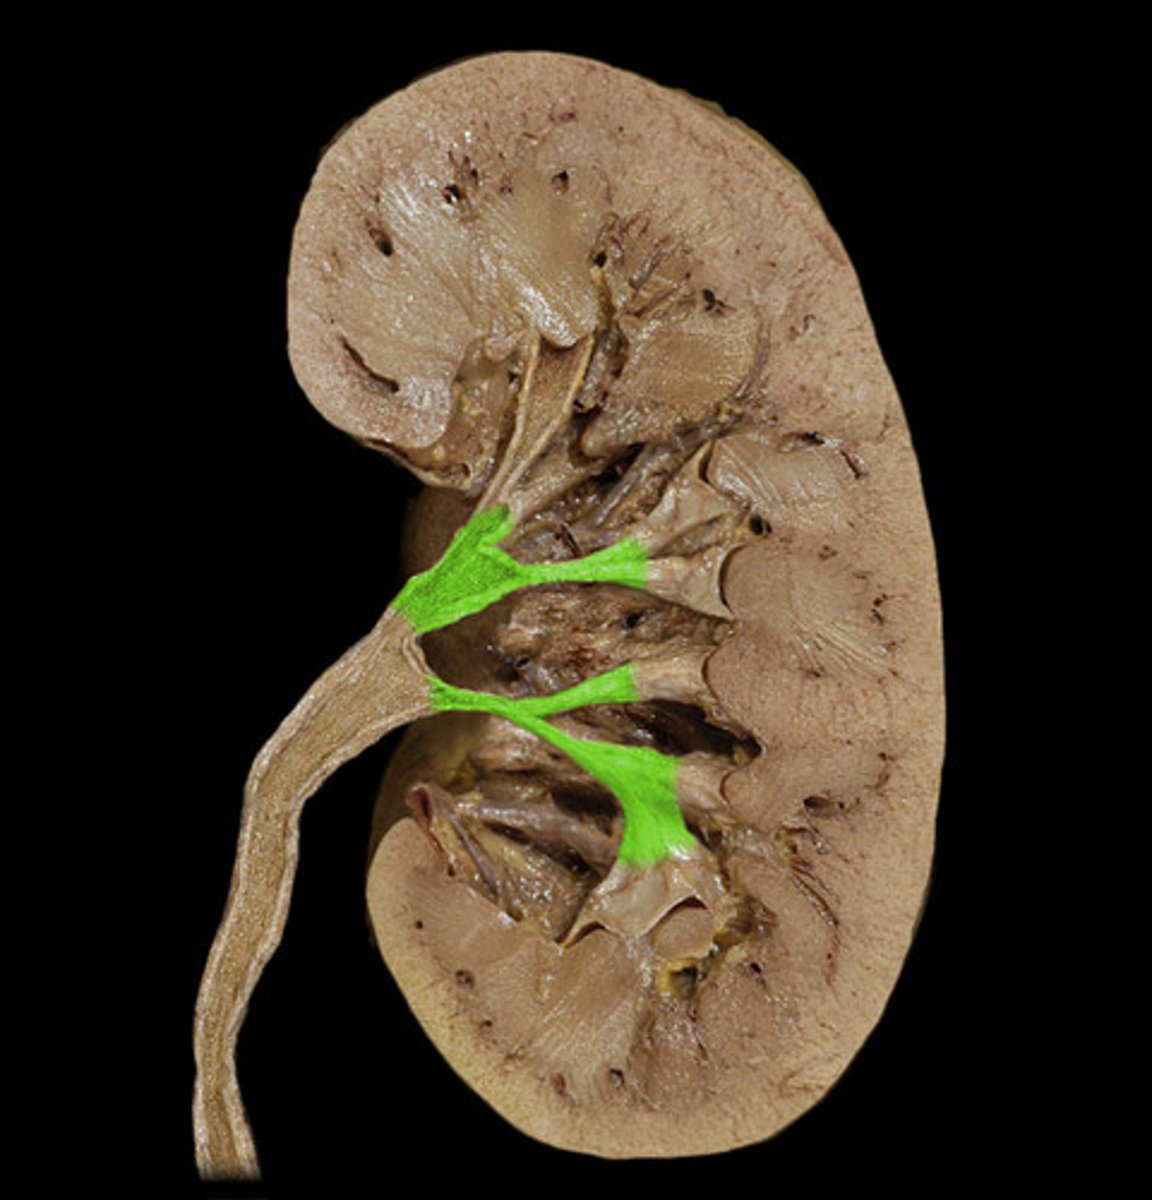

Renal vein

What is this?

Renal artery

Renal pelvis

Renal capsule

Renal cortex

Renal columns

Minor calyx

Major calyx